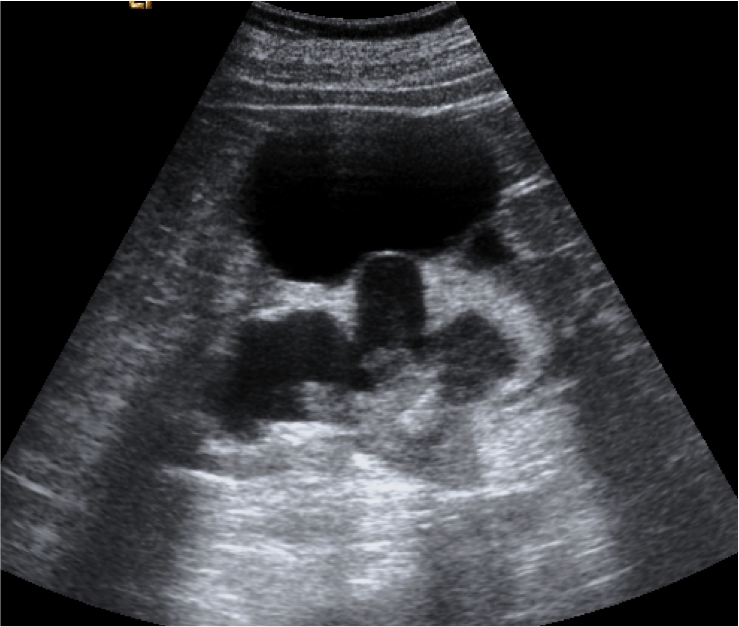

Ecografía:

- Debris ecogénicos en el interior del sistema colector: es es signos más fiable para diagnosticar una pionefrosis (S 90%, E 97%).

- Dilatación del sistema pielocalicial.

- Niveles líquido-líquido en el sistema colector.